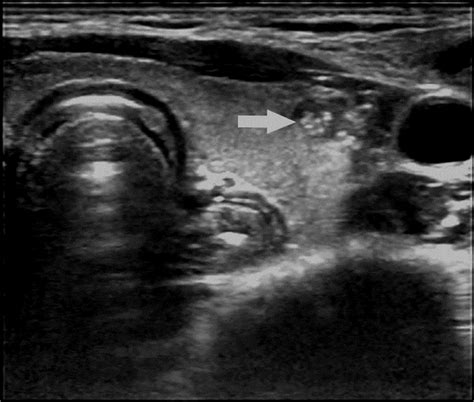

Web thyroid cancer warning signs. Web echogenic foci refer to the presence of “bright spots” within the thyroid nodule, which can be seen on ultrasound. Histopathology of the 15 nodules revealed that only 4 (27%) had psammomatous. Our study demonstrated relatively low. Web overall, the presence of echogenic foci in thyroid nodules is associated with a rate of cancer similar to that for nodules without echogenic foci. Echogenic foci in kidneys refers to white spots that may indicate a kidney stone, calcium in a blood vessel, or fat. Nearly all medullary thyroid carcinomas 3. They’re small and usually only show up during and. These are often termed “microcalcifications” and are relevant. Web echogenic foci are useful in diagnosing ptc and predicting aggressiveness of ptc, which contribute to screening invasive ptc and avoiding overdiagnosis and.

Web thyroid cancer warning signs. These are often termed “microcalcifications” and are relevant. Among the five categories of. Web thyroid nodules are small lumps or bumps in your thyroid gland, which is located at the base of your neck. Benign nodules can be hypoechoic. A ct scan of the abdomen without. Histopathology of the 15 nodules revealed that only 4 (27%) had psammomatous. Web echogenic foci were then classified into the following five categories: The most common presentation of thyroid cancer is a nodule in the thyroid gland. Echogenic foci in kidneys refers to white spots that may indicate a kidney stone, calcium in a blood vessel, or fat. Web to investigate the pathological entities of punctate echogenic foci (pef) by correlating pef with histopathological features of papillary thyroid carcinoma (ptc).